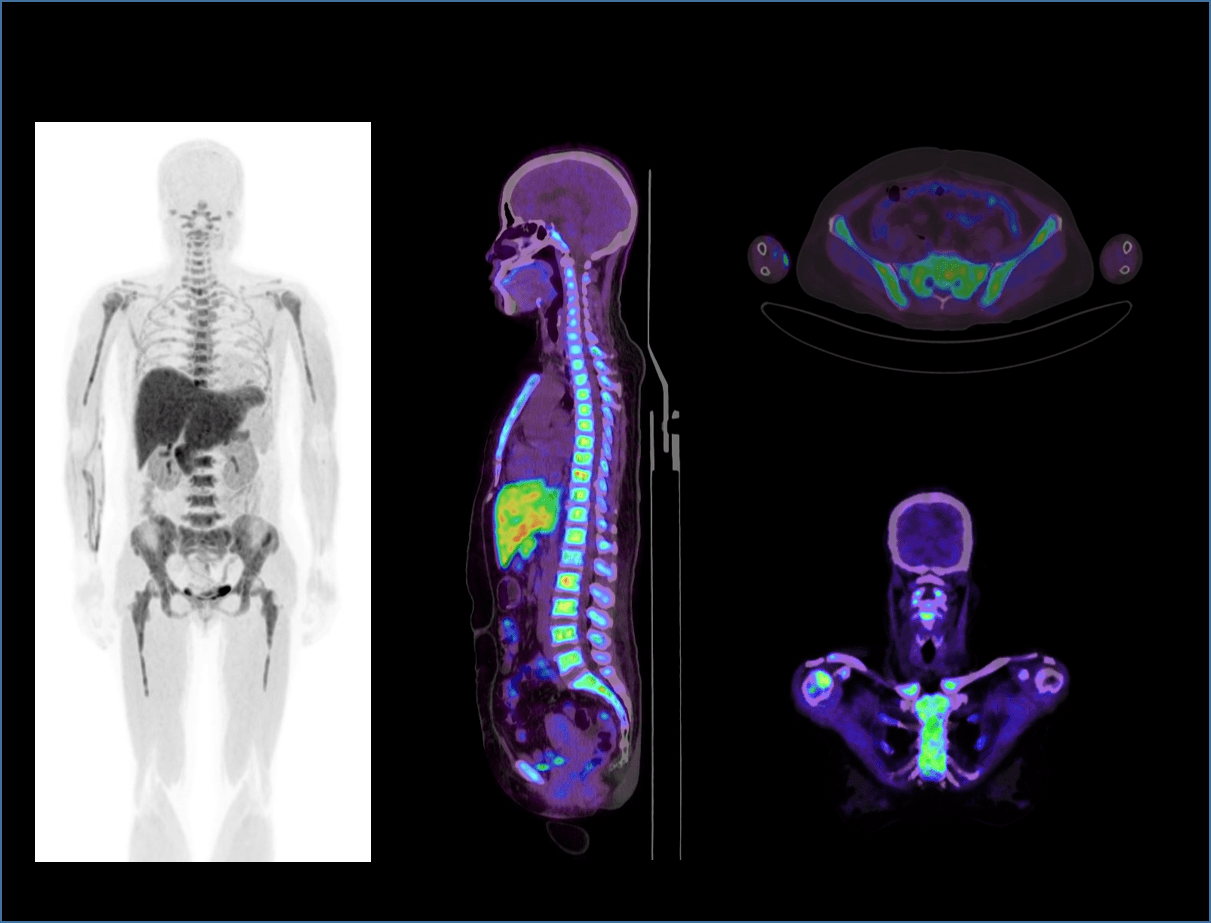

TOF + PSF

超大矩阵,高精度超清重建